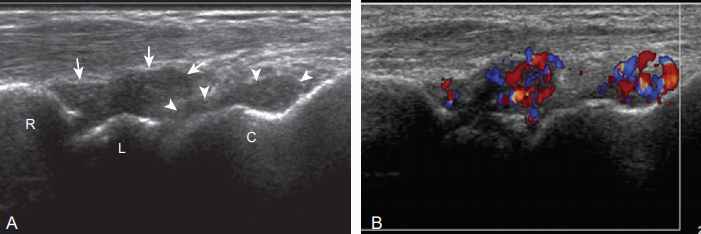

팽창된 관절오목내에 에코가 보이는 경우, 복합액과 윤활막염(synovitis)을 고려해야 한다. 두 원인 간의 구분은 어려울 수 있으며, 근육에 비해 낮은에코, 같은 에코, 또는 높은 에코 등 다양하게 보일 수 있다. 만약 관절오목 팽창이 탐촉자에 의한 압박으로 눌리거나 관절운동에 따라 내부에코가 움직이거나 또는 강화도플러영상(power doppler)에서 내부에 혈류가 보이지 않으면 복합액의 가능성이 높다. 반면에 관절오목이 거의 눌리지 않거나 색 및 강화 도플러 영상에서 혈류가 보이면 윤활막염의 가능성이 높다. 감별을 위하여 초음파유도하 흡인이 필요할 수 있다. 복합액과 윤활막염은 출혈, 판누스(pannus), 그리고 감염, 염증성관절염, 결정체(crystal) 침착에 의한 염증 등이 원인이다. 색소침착융모결절성 윤활막염(pigmented villonodular synovitis)과 윤활막뼈연골종증(synovial osteochondromatosis)등의 윤활막 증식성 질환도 원인이 될 수 있다. 이외에 윤활막 조직에 높은 에코 석회화가 생길 수도 있다.

윤활막염(synovitis) 만약 염증성 윤활막염이 의심되면 낮은에코의 관절연골과 뼈까짐(bone erosion)에 대해 검사하는 것이 중요하며, 관절연골이 얇아지거나 결손이 보일 수 있다. 정상 뼈표면의 매끄러운 높은 에코 연결성이 끊기거나 불규칙한 부분이 보이면 뼈 까지을 시사 한다. 이소견은 비특이적이며 통풍, 결정체 침착과 관련된 관절염, 전신 염증성관절염 등의 가능성을 고려해야 한다. 뼈까지 의심되는 경우, 그 주위에 윤활막염이 동반되어 있으면 가능성이 높다. 먼쪽 손허리뼈의 움푹 파인 부분과 불규칙한 뼈겉돌기(osteophyte)를 뼈까짐으로 오인할 수 있으며 증상이 없는 관절과 비교하거나 단순촬영이 구분에 도움이 된다. 초음파는 손과 손목의 뼈 까짐을 발견하는데 단순촬영보다 민감하며, 윤활막두께와 혈류증가를 볼 수 있는 장점이 있다. 세모섬유연골에 의해 먼쪽 노자관절과 노손목관절이 분리된다. 세모섬유연골은 정상에서 균일한 두께를 가지는 높은 에코 구조물로 보이지만, 만성 변성 또는 얇아짐과 급성 절단 또는 틈 등의 병변이 생길 수 있다. 작은 급성 째짐, 특히 노뼈 부착부위의 째짐은 진단이 어려울 수 있다.